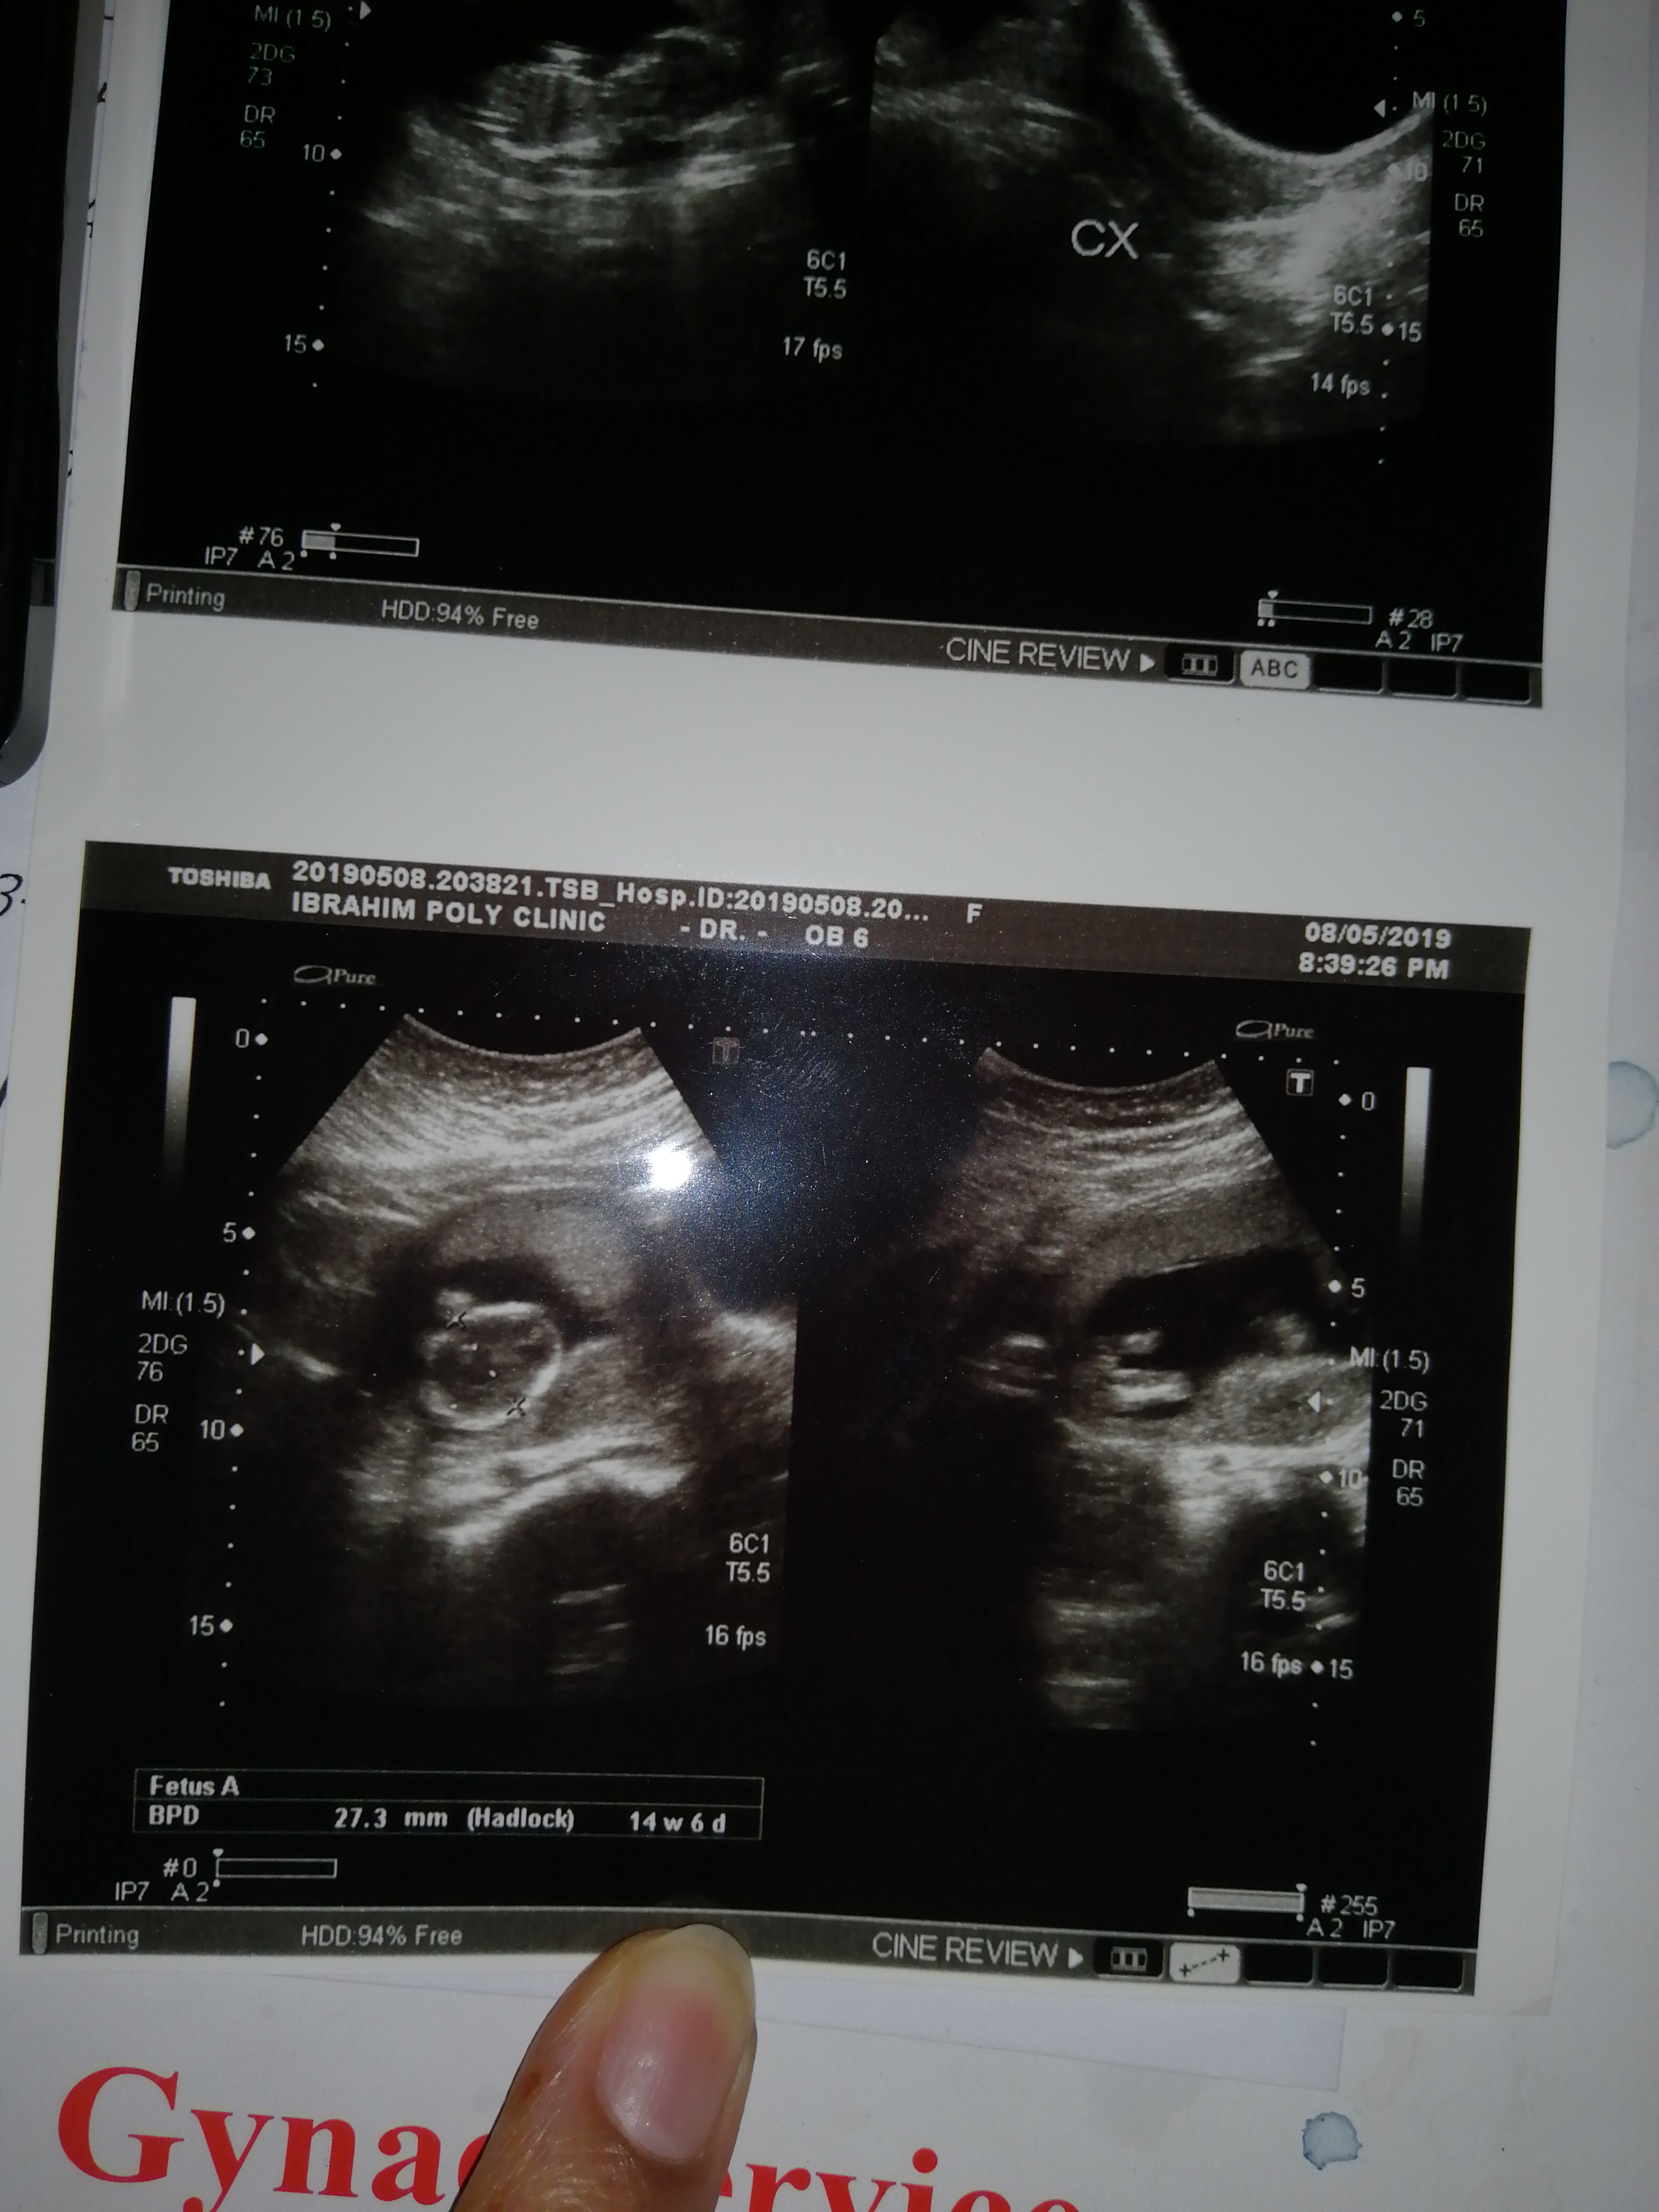

Want to know the scan report and gender of baby

It is not possible to report gender on films alone.  Ask your radiologist who conducted the study to let you know.

Difficult to comment on sex after only seeing the films